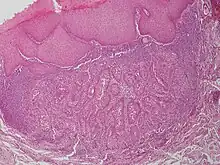

Warty dyskeratoma

Warty dyskeratoma, also known as an Isolated dyskeratosis follicularis,[1]: 777 is a benign[2] epidermal proliferation with distinctive histologic findings that may mimic invasive squamous cell carcinoma[3] and commonly manifests as an umbilicated (Having a central mark or depression resembling a navel) lesion with a keratotic plug,[4] WD have some histopathologic similarities to viral warts but it's not caused by HPV and the majority of these lesions display overall histopathologic features consistent with a follicular adnexal neoplasm.[5] Usually limited to the head, neck,[6] scalp[7] or face and vulva.[6] Lesions are generally solitary and sporadic and may be associated with a follicular unit. Oral involvement,[4] particularly the hard palate, and genital involvement have been reported. it can also be thought of as one of the manifestations of focal acantholytic dyskeratosis, an epidermal reaction pattern that can be seen in several disorders, including Darier's disease and Grover's disease.[8]: 639 But the main Difference between Darier disease and Warty dyskeratoma, is that Darier disease inherited dermatosis (autosomal dominant) consisting of multiple keratotic papules on the face, trunk, and extremities, while WD occurs as an isolated, noninherited, single keratotic nodule mainly confined to the head and neck as mentioned earlier.[6]